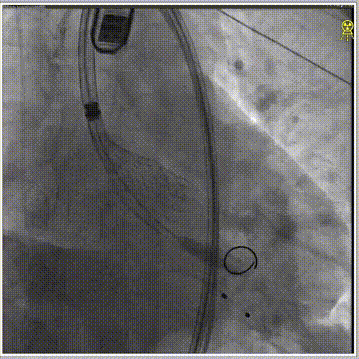

经左股动脉穿刺,置入6F股动脉穿刺鞘,将猪尾导管引导至主动脉根部,行主动脉造影。180bpm下置入23mm球囊扩张,沿导丝送入美敦力Evolut PRO经导管主动脉瓣膜系统,采用美敦力独有的commissual alignment技术,最大程度保护冠脉。递送系统顺利送入动脉系统并顺利过弓跨瓣,在采用世界先进的Cusp Overlap技术植入技术,最终目标位置完美释放,瓣膜立即工作,展开形态良好,无瓣周漏,无冠脉阻挡,无传导阻滞发生,术后无压差,血液动力学稳定,手术圆满成功。

球囊预扩